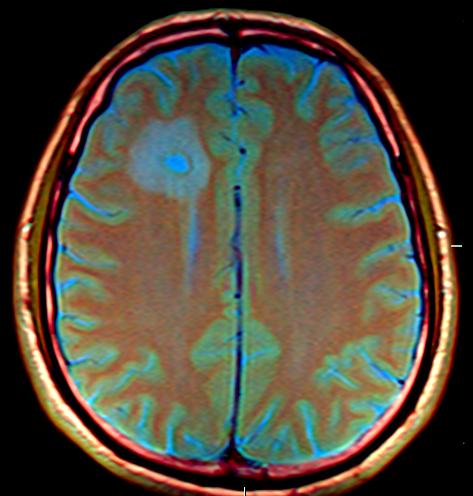

Brain MRI

PHOTO COURTESY OF WIKIMEDIA